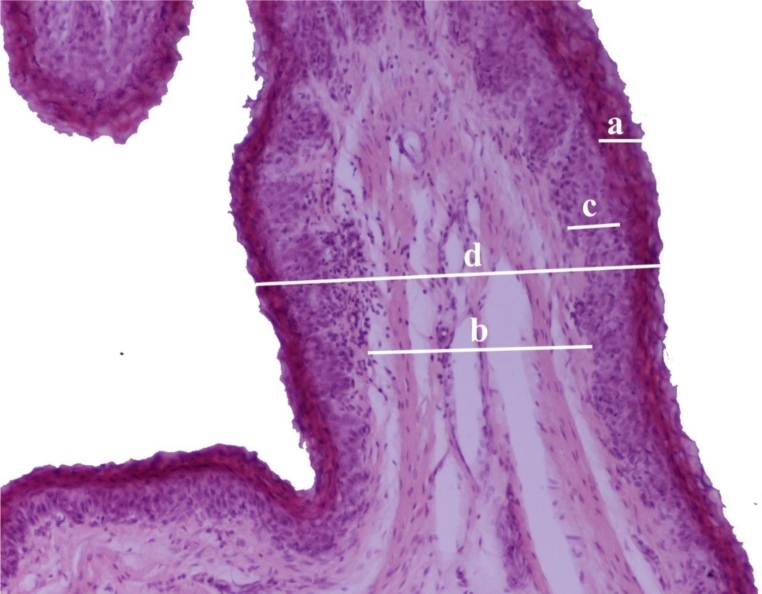

For histological examinations, the rumen wall samples were cut into 1 × 1 cm particles and fixed in 10% formalin buffer for 48 to 72 h. Afterward, they were dehydrated using alcohol solutions and routinely embedded in paraffin (Paraplast Plus®, Kendall, England). Dewaxed 3–5 μm-thick sections were stained with hematoxylin and eosin (H&E) for histopathological evaluation. From each sample, randomly selected fields with a x10 objective were captured with a microscope-coupled camera, and ImageJ software was used to measure stratum corneum thickness, connective tissue width, non-keratinized epithelium thickness, and total epithelium thickness in each photomicrograph (Fig. 3).

Fig. 3.

Measurements of the beef ruminal papillae: (a) Stratum corneum thickness. (b) Width of the connective tissue. (c) Thickness of the non-keratinized epithelium. (d) Total epithelium thickness. (Hematoxylin-eosin staining; magnification x10)